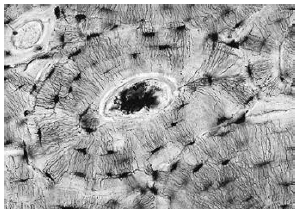

Складником якої системи органів людини є зображена тканина?